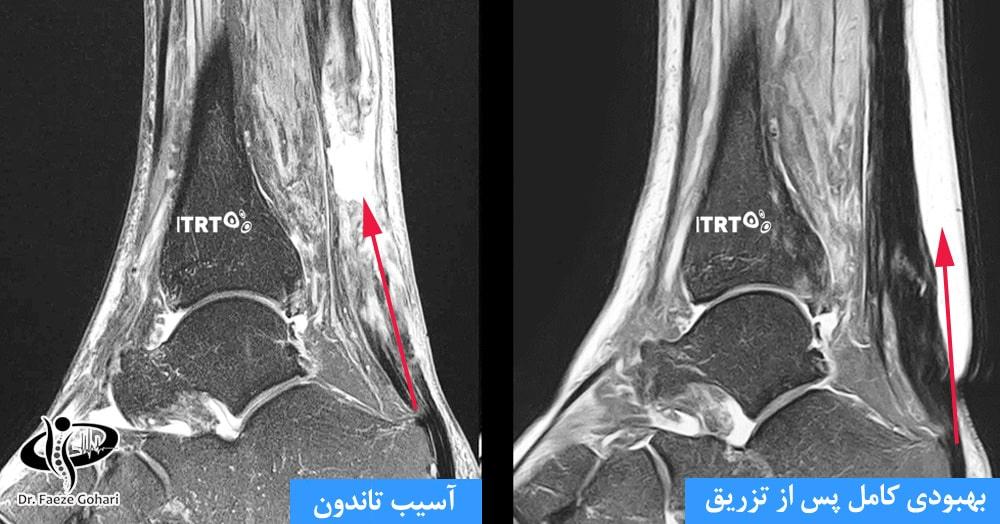

درمان تاندونیت یا پارگی‌های ناکامل تاندون آشیل، چه در محل اتصال به پاشنه و چه در بافت میانی، از طریق تزریق سلول‌های بنیادی و پی آر پی (PRP) یکی از مؤثرترین روش‌های غیرجراحی است که علاوه بر کاهش درد، به بازسازی طبیعی بافت آسیب‌دیده کمک می‌کند.

یکی از مزایای منحصربه‌فرد سلول‌درمانی، امکان درمان هم‌زمان آسیب‌های همراه با تاندون است. به طور مثال، اگر رباط مچ پا دچار پارگی یا آسیب‌دیدگی شده باشد، باعث ایجاد ورم و ناپایداری مچ پا شود یا التهاب بورس وجود داشته باشد، سلول‌درمانی می‌تواند پس از تنها دو روز به کاهش چشمگیر درد و التهاب کمک کند. همچنین، با تکمیل دوره درمان که ممکن است شامل یک یا دو جلسه تزریق باشد، بازسازی کامل بافت تاندون و بازگشت به فعالیت‌های ورزشی با کمترین خطر آسیب مجدد امکان‌پذیر خواهد بود.

تحقیقات نشان می‌دهند، درمان‌های نوین مانند تزریق PRP (پلاسمای غنی از پلاکت) و سلول‌های بنیادی،  به‌عنوان روش‌های بازسازی طبیعی، نه‌تنها به بهبود علائم کمک می‌کنند، بلکه از لحاظ ساختاری نیز موجب ترمیم و تقویت بافت آسیب‌دیده تاندون می‌شوند. به‌عنوان روش‌های بازسازی طبیعی، نه‌تنها به بهبود علائم کمک می‌کنند، بلکه از لحاظ ساختاری نیز موجب ترمیم و تقویت بافت آسیب‌دیده تاندون می‌شوند. این روش‌ها بهترین نتایج را در افراد زیر ۷۰ سال نشان داده‌اند. کاهش علائم معمولاً از دو روز پس از درمان به طور قابل‌توجهی آغاز می‌شود و فرایند بازسازی و ترمیم بافت تا ۶ ماه در بدن ادامه دارد.